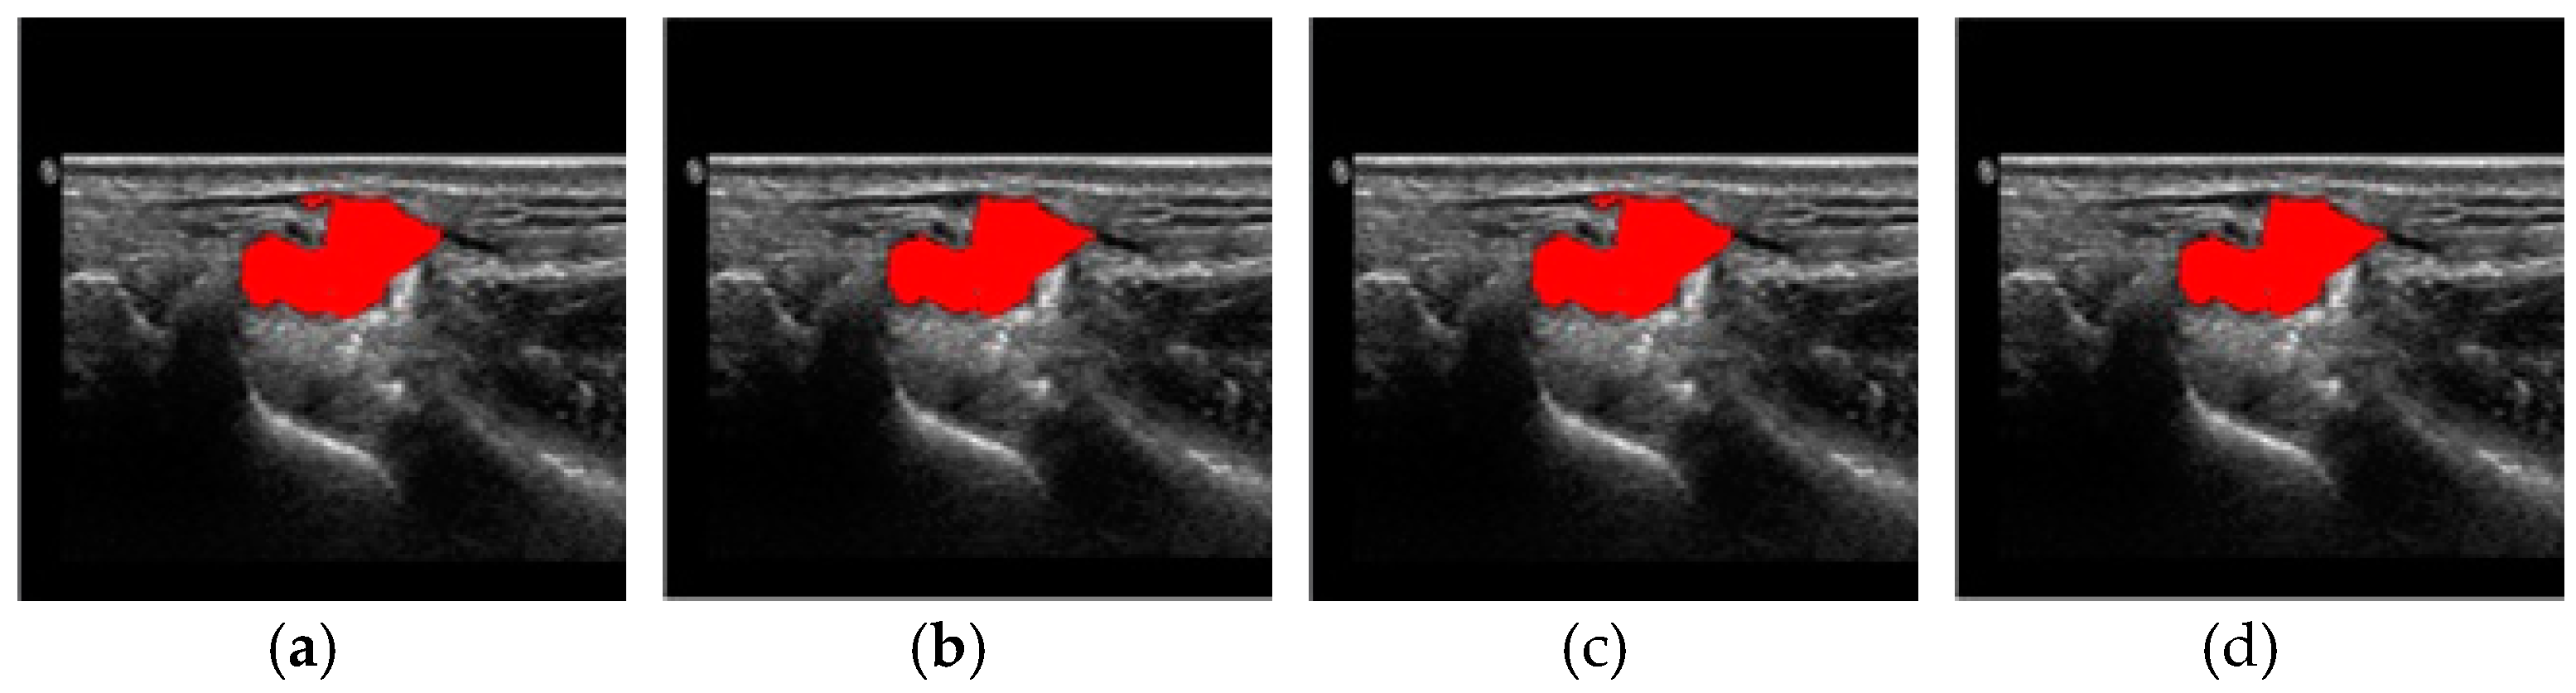

4. Results and Discussion

| Method | ART2 | FCM | ||

|---|---|---|---|---|

| # of Images | Vigilance Parameter | # of Clusters | Weight | # of Initial Clusters |

| 90 | 0.1 | 16 | 2 | 10 |

| Method | ART2 [23] | FCM |

|---|---|---|

| Correct | 80 | 86 |

| Incorrect | 10 | 4 |

| Accuracy (%) | 88.9 | 95.6 |